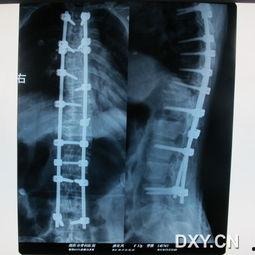

张先生患有重度脊柱弯曲,经过一段时间的正骨视频练习,他的脊柱弯曲得到了一定程度的改善,生活质量也得到了提高。